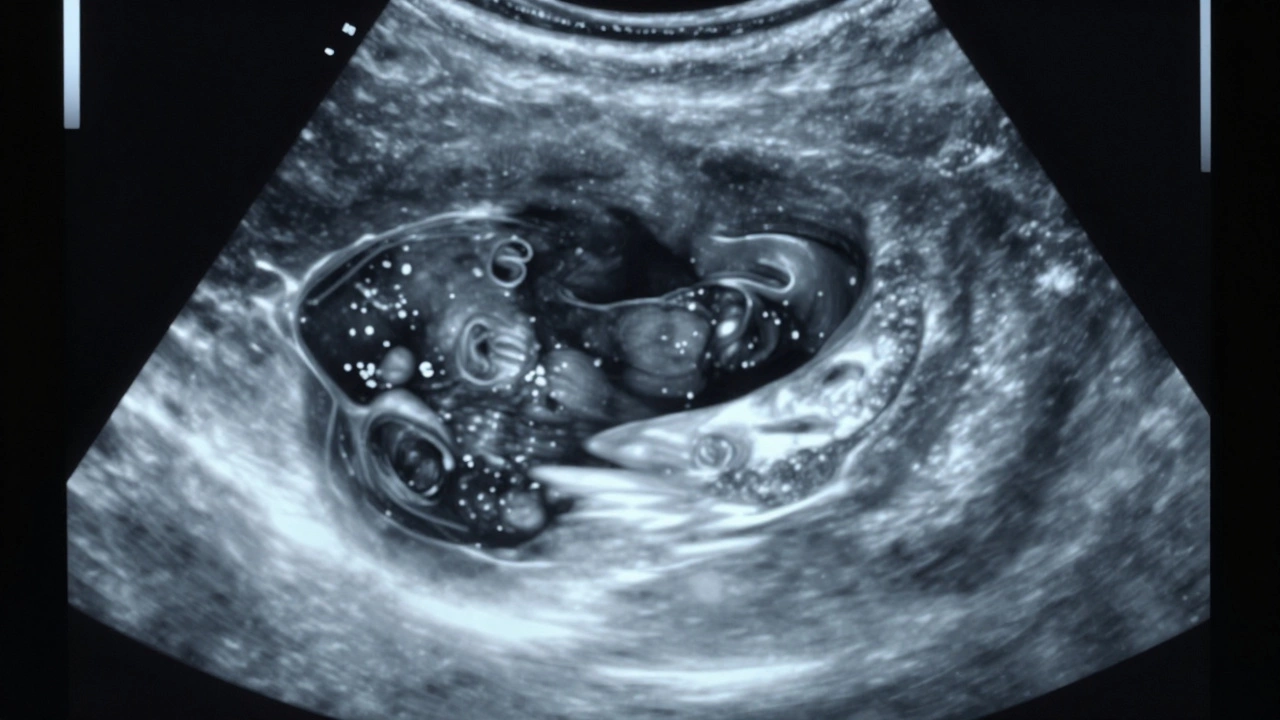

Иногда киста выглядит не так идеально. Она может содержать небольшие включения, перегородки или утолщенные стенки. Такие образования называют сложными кистами. Они не всегда опасны, но требуют внимания.

На УЗИ сложная киста может иметь:

• Небольшие внутренние перегородки - тонкие, но видимые линии внутри полости.

• Мелкие эхогенные включения - точки или комочки, которые отражают ультразвук. Это могут быть сгустки слизи или кровь.

• Утолщенные стенки - более чем 3 мм, с неровностями.

• Слабый кровоток на краях - это не внутри, а только по периметру.

Сложные кисты чаще встречаются в молочной железе или яичниках у женщин после 50 лет. В 80% случаев они все равно остаются доброкачественными, но врач может назначить повторное УЗИ через 3-6 месяцев или взять анализ на онкомаркеры.

Сложная киста молочной железы на УЗИ: внутренние перегородки и мелкие включения с слабым кровотоком по краям.